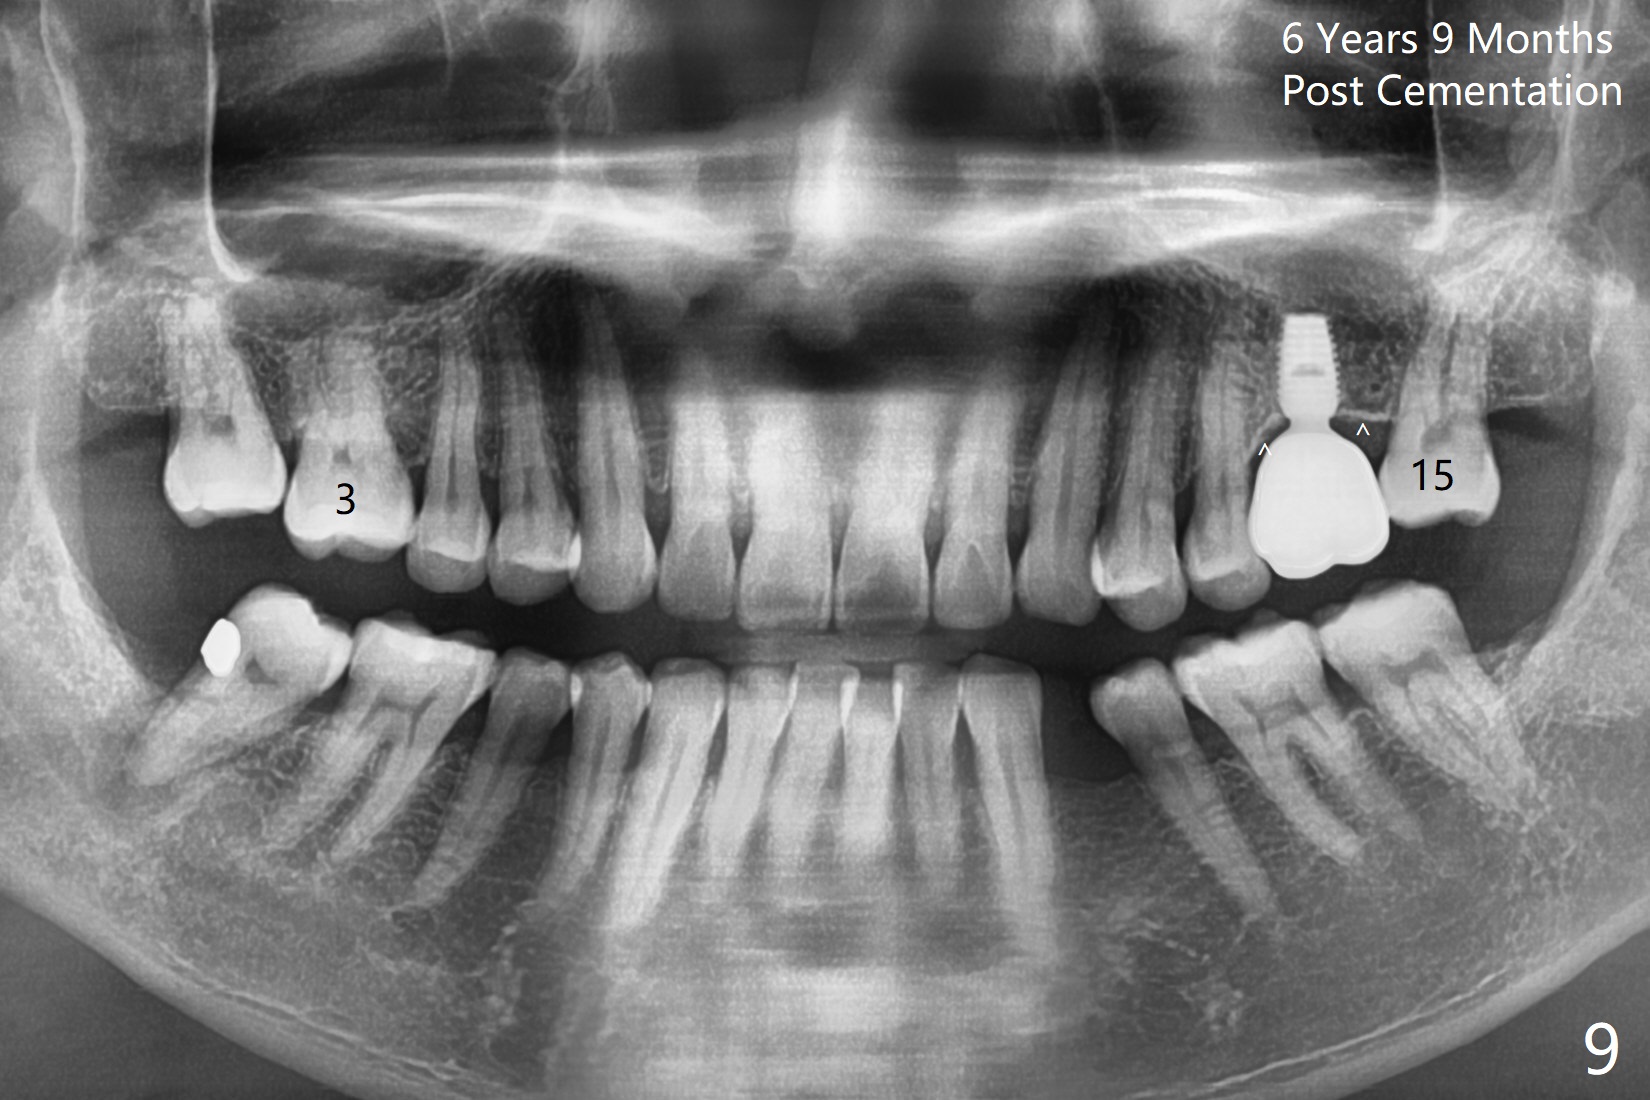

A 49-year-old man is an engineer. The tooth #14 is missing (Fig.1,2). He wonders how a one-rooted implant can replace a three-rooted tooth. Anyway, osteotomy is initiated at the site with 2.5 mm reamer in place (Fig.3). A 5x8 mm Bicon implant is placed (Fig.4). Seven and a half months later, the bone density next to the implant plateau appears to increase (Fig.5 arrowheads, as compared to Fig.4). The beauty of Bicon implant is that the crown (Fig.6 C) can be extraorally cemented to the abutment (A) prior to re-seating. Two years and 3 months post cementation, while no residual cement is visible, the bone density at the crest has increased (Fig.7 arrowheads). The crown is de-cemented 4 years 4 months post cementation; it appears that the abutment is small and short (5x2 mm 10 degree stealth). The bone density of the cortex around the implant (Fig.9 ^) is higher than that at #15 and #3.